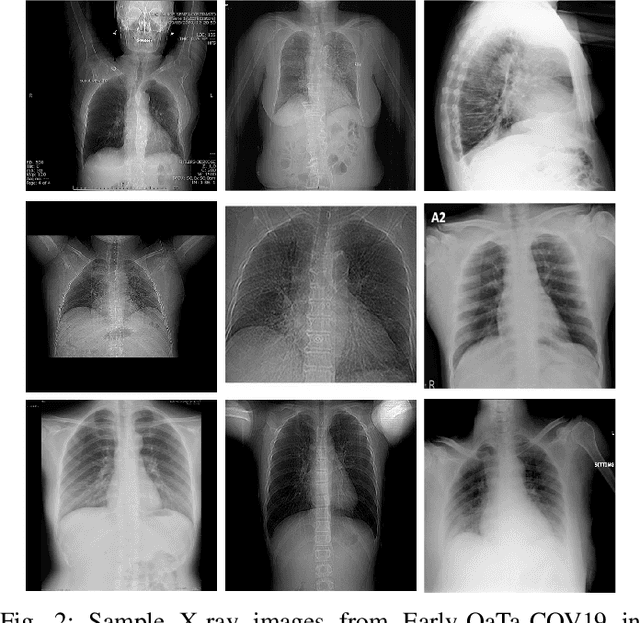

In this study, our first aim is to evaluate the ability of recent state-of-the-art Machine Learning techniques to early detect COVID-19 from plain chest X-ray images. Both compact classifiers and deep learning approaches are considered in this study. Furthermore, we propose a recent compact classifier, Convolutional Support Estimator Network (CSEN) approach for this purpose since it is well-suited for a scarce-data classification task. Finally, this study introduces a new benchmark dataset called Early-QaTa-COV19, which consists of 175 early-stage COVID-19 Pneumonia samples (very limited or no infection signs) labelled by the medical doctors and 1579 samples for control (normal) class. A detailed set of experiments show that the CSEN achieves the top (over 98.5%) sensitivity with over 96% specificity. Moreover, transfer learning over the deep CheXNet fine-tuned with the augmented data produces the leading performance among other deep networks with 97.14% sensitivity and 99.49% specificity.